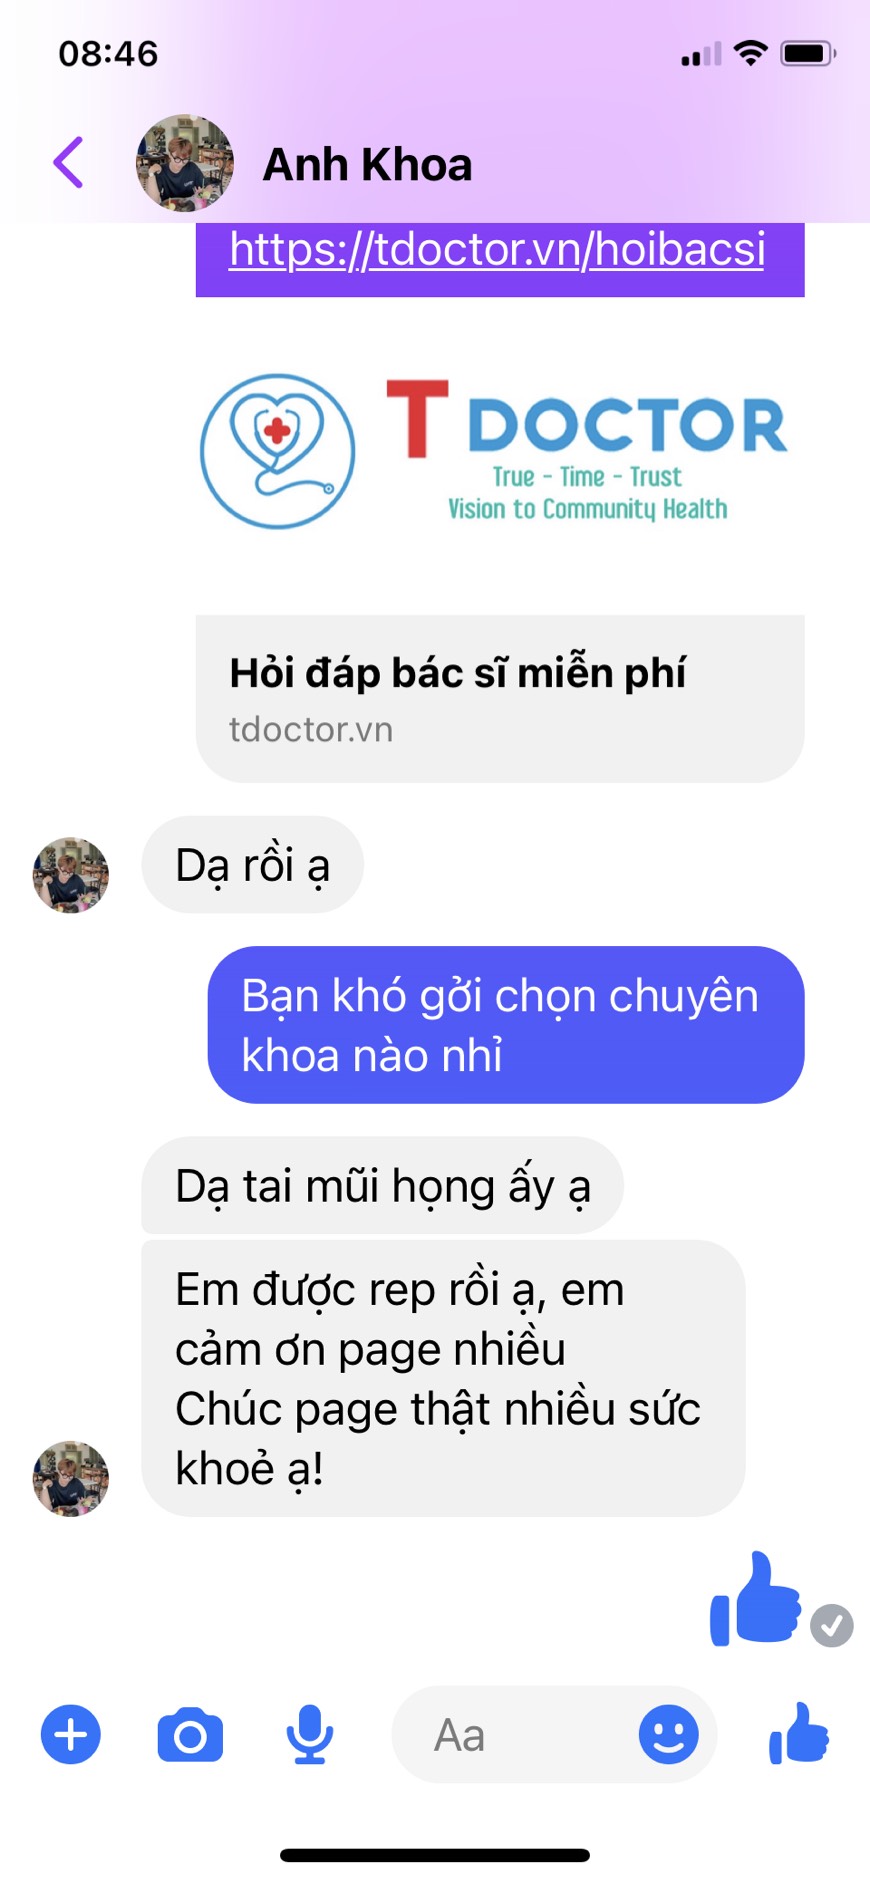

Hỏi đáp trực tiếp với bác sĩ uy tín

Đặt câu hỏi miễn phí

Đặt câu hỏi miễn phí

Hơn 1000 Bác sĩ đang sẵn sàng giúp đỡ bạn

Tiến sỹ, Bác sĩ Nguyễn Ngọc Minh

Giảng Viên chuyên khoa TMH Trường Đại Học Y khoa Phạm Ngọc Thạch